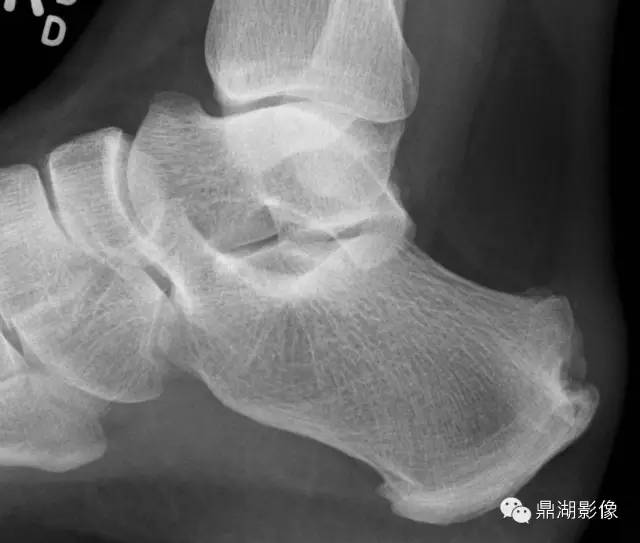

“食蚁兽鼻征”即在足侧位片跟骨前突过长,超过跟骰关节面水平,此征象对诊断跟舟骨桥有很大的帮助,于1987年首先由Oestreich等人提出来。有报道称“反食蚁兽鼻征”,即舟骨向后外侧伸长突出,诊断跟舟骨桥的特异性达 100%

左图为食蚁兽鼻征,右图为正常